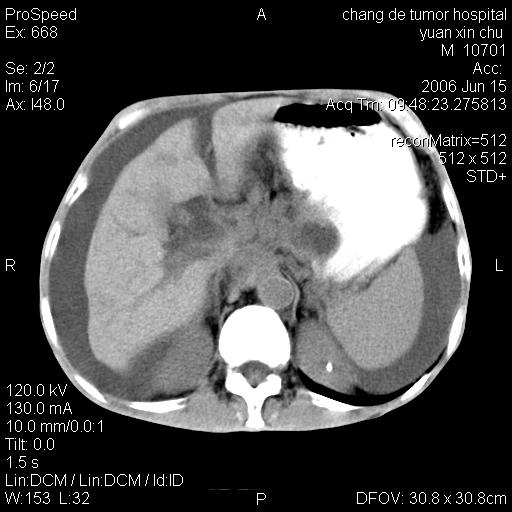

以下是引用qian在2007-4-23 19:06:00的发言:[br]胰腺体积增大,轮廓欠规则,肝轮廓波浪状改变,肝裂增宽,肝周、脾周有液性密度,腹膜后肿大淋巴结,考虑1、胰腺癌伴腹膜后淋巴结转移;2、肝硬化伴腹水。

以下是引用卜一在2007-4-23 20:12:00的发言:[br]胰腺体积增大,轮廓欠规则,肝轮廓波浪状改变,肝裂增宽,肝周、脾周有液性密度,腹膜后肿大淋巴结,考虑1、胰腺癌伴腹膜后淋巴结转移;2、肝硬化伴腹水。支持!